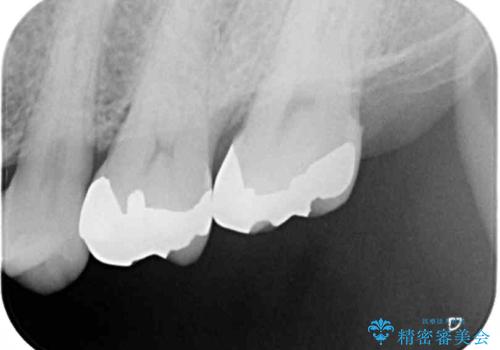

ゴールドインレーは銀歯のインレーやセラミックインレーと比べ、「技工操作の精度が高く、適合が著しく良い」というメリットがあります。特に上の奥歯は歯科医師の操作が行いにくいため、「適合の良さ」は再治療のリスクを防ぐ上でとても重要な要素となります。

上の奥歯は金属色が見えることもないため、審美的な問題は全くありません。